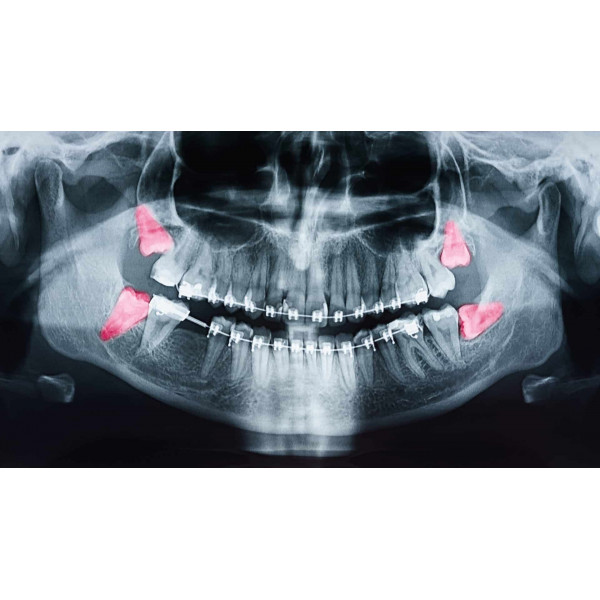

Sự sai lệch này dẫn đến áp lực bất thường trong quá trình mọc răng, khiến răng khôn đâm vào răng số 7 hoặc mọc ngầm trong xương. Nếu không phát hiện sớm, nó có thể gây đau răng khôn, viêm nướu và tiêu xương cục bộ. Việc chẩn đoán hình thể xương hàm bằng phim X-quang toàn cảnh giúp bác sĩ xác định chính xác hướng mọc để lên kế hoạch điều trị răng khôn mọc lệch phù hợp.

Tình trạng này thường gây đau răng khôn tái phát do mô nướu bị viêm nhiễm và áp lực giữa các răng tăng cao. Để điều trị răng khôn mọc lệch hiệu quả, bác sĩ cần đánh giá tương quan giữa các răng cối và hình dạng xương hàm thông qua phim Cone Beam CT 3D, từ đó xác định hướng phẫu thuật an toàn và ít sang chấn nhất.

Chẩn đoán chính xác là yếu tố tiên quyết trong điều trị răng khôn mọc lệch. Bác sĩ thường chỉ định chụp phim X-quang Panorama hoặc Cone Beam CT 3D để xác định hướng mọc, độ sâu, khoảng cách đến ống thần kinh và mức độ tiêu xương. Việc đánh giá lâm sàng kèm hình ảnh giúp tiên lượng mức độ khó và chọn phương pháp phẫu thuật phù hợp.